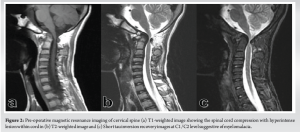

A 14-year-old boy presented to the spine clinic with progressive weakness of the bilateral upper limb, progressing to bilateral lower limb for the past 1.5 years following trivial trauma to the neck and with bowel and bladder incontinence for the past 1 year. At presentation, he was not able to stand without support, had increased tone (modified Ashworth grade 1) in bilateral upper and lower limbs, with functional motor power present and no sensory deficit in any of the dermatomes. On elicitation, both upper and lower limb reflexes were exaggerated. Exaggerated pectoralis reflex and presence of scapulohumeral reflex suggested a clinical diagnosis of supra-axial cervical myelopathy. On further evaluation, special signs such as Hoffman’s sign and grasp-release test were positive. Cervical spine radiograph showed atlantoaxial subluxation with decreased posterior atlanto-dens interval along with fusion of C2 and C3 vertebrae (Fig. 1). On magnetic resonance imaging cervical spine, thecal sac and spinal cord compression at the level of C1/C2 joint with no visible cerebrospinal fluid rim was noted (Fig. 2). 3D Computed tomography angiography (CTA) of the cervical spine showed an incomplete anterior and posterior arch of the atlas with well-corticated bony fragments within the posterior arch defect. Note of fenestration of VA on right side and high-riding VA was also made (Fig. 3). A final diagnosis of supra-axial extradural compressive cervical myelopathy due to congenital atlantoaxial subluxation with anomalous VA (Nurick Grade 5) was made. The patient was planned for C1-C2 reduction and posterior instrumented fusion using C1 lateral mass and C2 laminar screws under intraoperative neuromonitoring. The patient was positioned prone on Mayfield, and a longitudinal midline approach from C1 to C3 was carried out, elevating the paraspinal muscle subperiosteally from the midline. A congenital defect in the posterior arch of C1 was noted. First, the left side C1 lateral mass screw was put after identifying the entry point. On the right side, the aberrant VA was freed from the posterior arch of C1 and retracted, inferiorly exposing the lateral mass of C1 along with facets of C1-C2 joint, and C1 lateral mass screw was inserted. Further, laminar screws were placed bilaterally in C2. C1 was reduced over C2 using rod cantilever mechanism and by applying compression force bilaterally between the C1 lateral mass and the C2 laminar screws. Decompression was achieved by removing the remaining C1 posterior arch and corticated bony fragment from the midline. Harvested local bone autograft was placed in the C1-C2 joint on the left side and the prepared fusion bed posteriorly (Figs. 4 and 5).